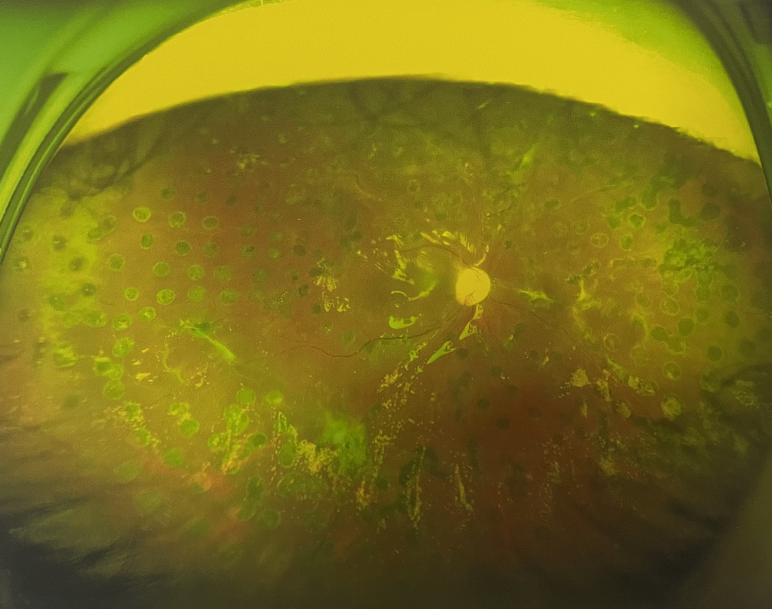

4個(gè)月后王女士來(lái)院取硅油,取油后視力恢復(fù)到0.6。“當(dāng)時(shí)來(lái)的時(shí)候真的只能看到模糊的影子,特別害怕覺(jué)得完了,想說(shuō)眼睛估計(jì)要瞎了,沒(méi)想到手術(shù)后視力竟然提升了,現(xiàn)在也看得比較清楚了。”王女士說(shuō)到。

張小虎醫(yī)生表示,糖網(wǎng)病進(jìn)展到嚴(yán)重增殖期帶來(lái)的視力損傷往往是極其嚴(yán)重的,目前王女士右眼從術(shù)前0.02恢復(fù)到術(shù)后0.6,已屬十分難得。

右眼術(shù)后